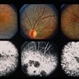

- 14-year-old white female. Congenital. 20/40.